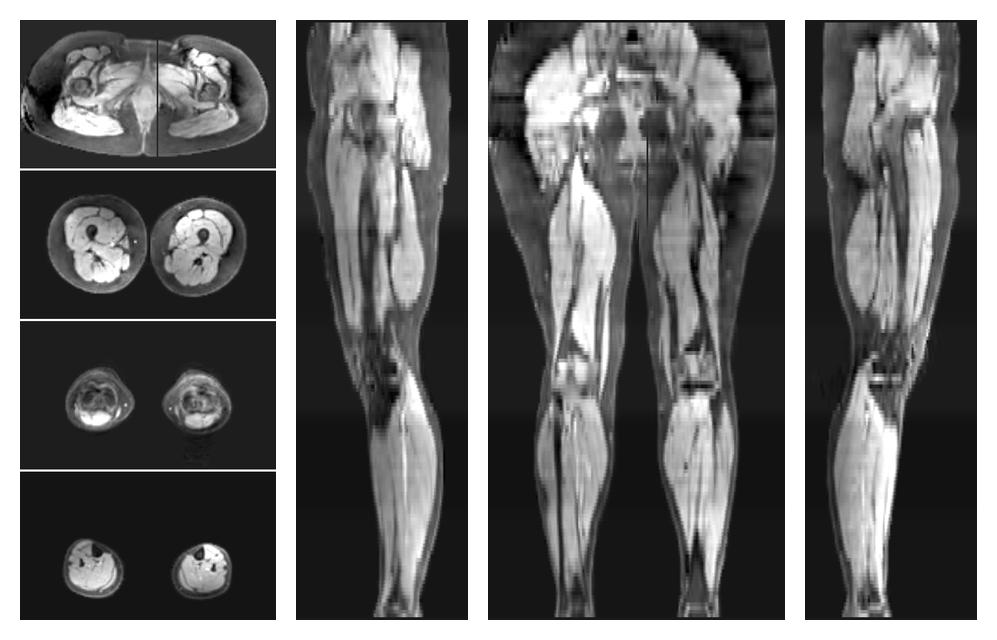

• Water only signal

The water part of the acquired multi-echo spin echo data.